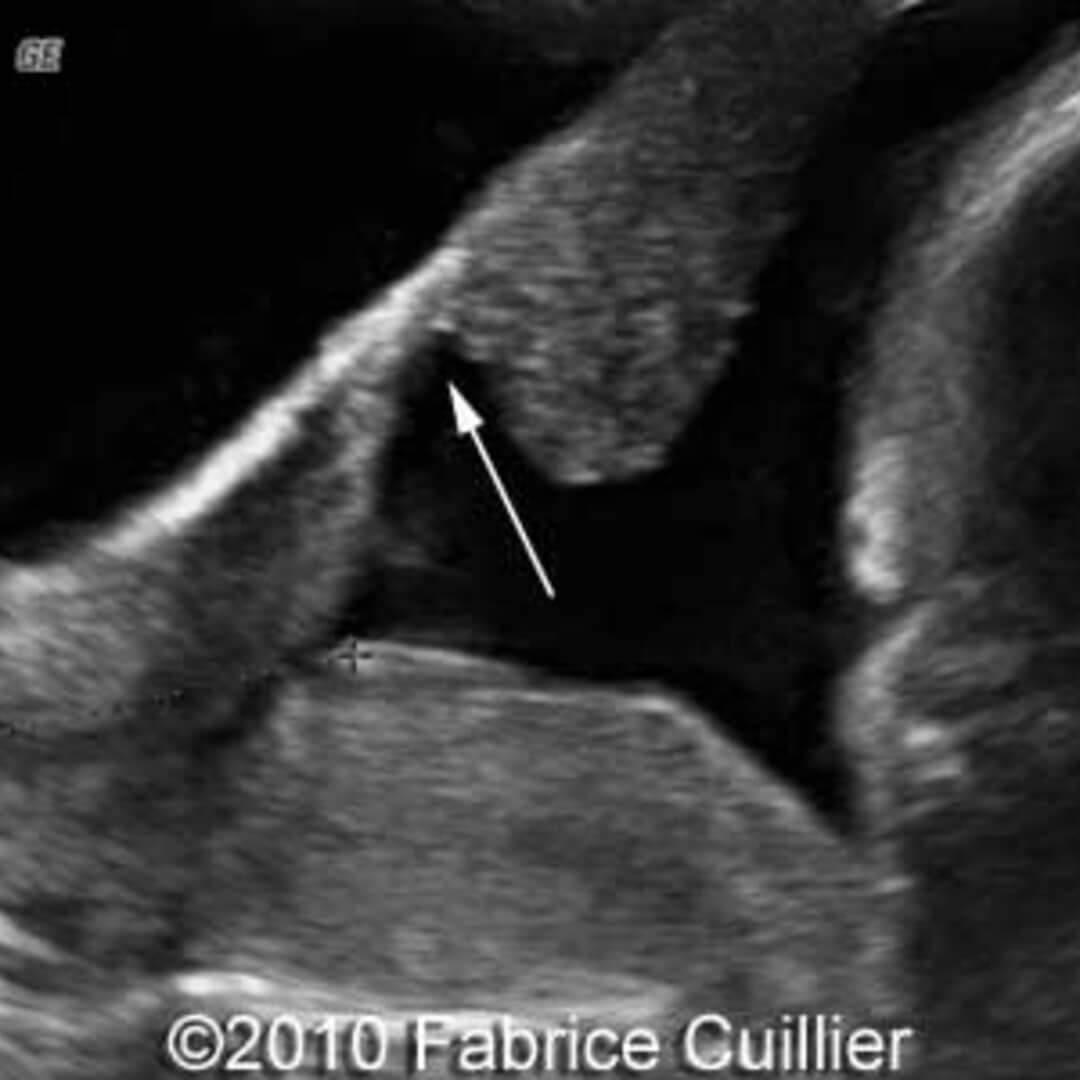

Uterine scar dehiscence following caesarean section » Obstetrics and

From thefetus.net

Uterine scar dehiscences (Cases 1 and 2) TVUS image (a) shows a light Scar Wound Dehiscence wound dehiscence is a surgical complication in which two sides of a surgical incision separate and rupture along the incision. — wound dehiscence is a surgery complication where the incision, a cut made during a surgical procedure,. It refers to when a surgical incision fails to heal correctly, resulting in the wound reopening. — dehiscence is a. Scar Wound Dehiscence.

Uterine scar dehiscences (Cases 1 and 2) TVUS image (a) shows a light Scar Wound Dehiscence It's also known as wound. — dehiscence is a surgical complication in which the edges of a wound no longer meet. — surgical wound dehiscence (swd) impacts on mortality and morbidity rates and significantly contributes to. It refers to when a surgical incision fails to heal correctly, resulting in the wound reopening. — wound dehiscence is a. Scar Wound Dehiscence.

From radiopaedia.org

Uterine cesarean scar dehiscence Image Scar Wound Dehiscence It's also known as wound. — wound dehiscence describes a potential complication of surgery. — wound dehiscence is a surgery complication where the incision, a cut made during a surgical procedure,. — surgical wound dehiscence (swd) impacts on mortality and morbidity rates and significantly contributes to. — dehiscence is a surgical complication in which the edges. Scar Wound Dehiscence.